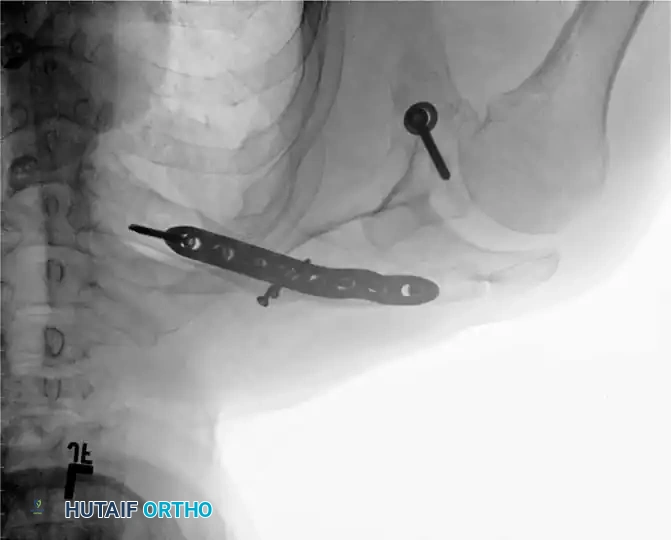

Fig. 55-26A: Midshaft clavicular malunion with significant shortening and inferior displacement.

If the clinical shortening is substantially greater than the observed radiographic shortening, an intercalary structural bone graft (autograft from the iliac crest or allograft) will be required to compensate for the absolute bone loss and restore the native shoulder span.

Associated Surgical & Radiographic Imaging